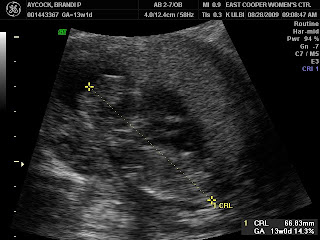

So today I went in for my first trimester screening and ultrasound. Our doctor recommended the screening based on some family history, not because anything is high risk :) The ultrasound piece looked great and we get the results from the blood test next Friday. Here are a few ultrasound photos for your viewing pleasure: